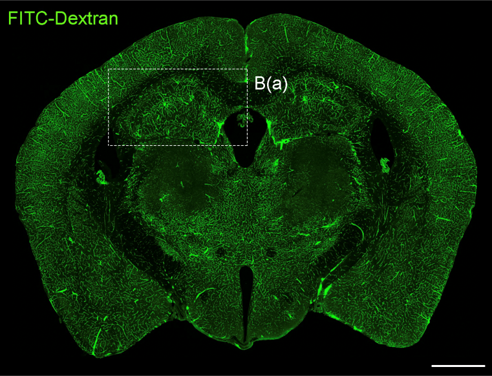

뇌혈관장애 및 퇴행성뇌질환 개선연구

- 연구주제 : 뇌혈관장애-유래 인지기능 저하 및 근감소증 제어기전 연구

- 연구주제 : 뇌경색 동물모델 구축을 통한 뇌혈관 장애 및 염증제어 후보물질 발굴